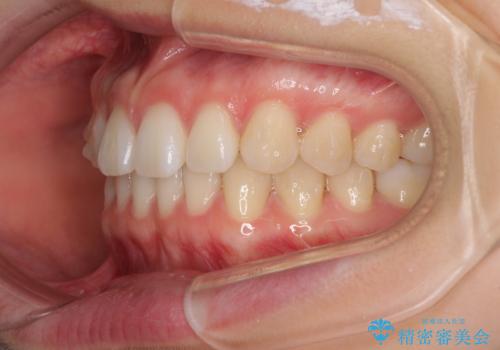

インビザラインによるすきっ歯の改善

- 上の前歯の隙間を気にして来院された患者様です。

インビザラインにより、隙間を閉じながら、隙間の原因であるディープバイトを改善していくこととしました。

下顎の歯列が強く上顎に咬みこむことで隙間ができてしまうため、マウスピースの保定装置では後戻りのリスクが高くなってしまいます。

そのため、上下ともに前歯の裏側を細いワイヤーで固定し、その上から保定装置のマウスピースを使用していただくこととしました。